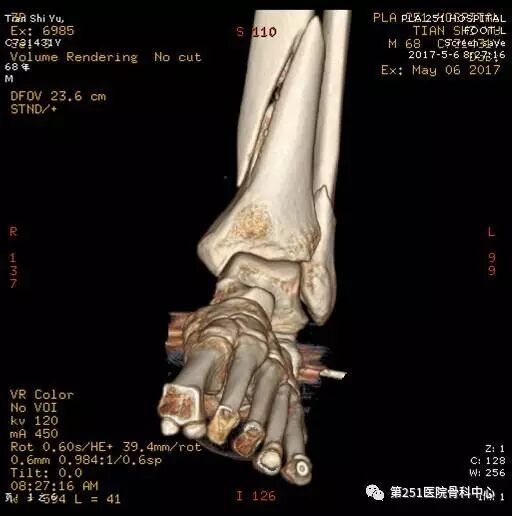

病例9:男性、68岁、车祸伤,胫腓骨远端骨折。